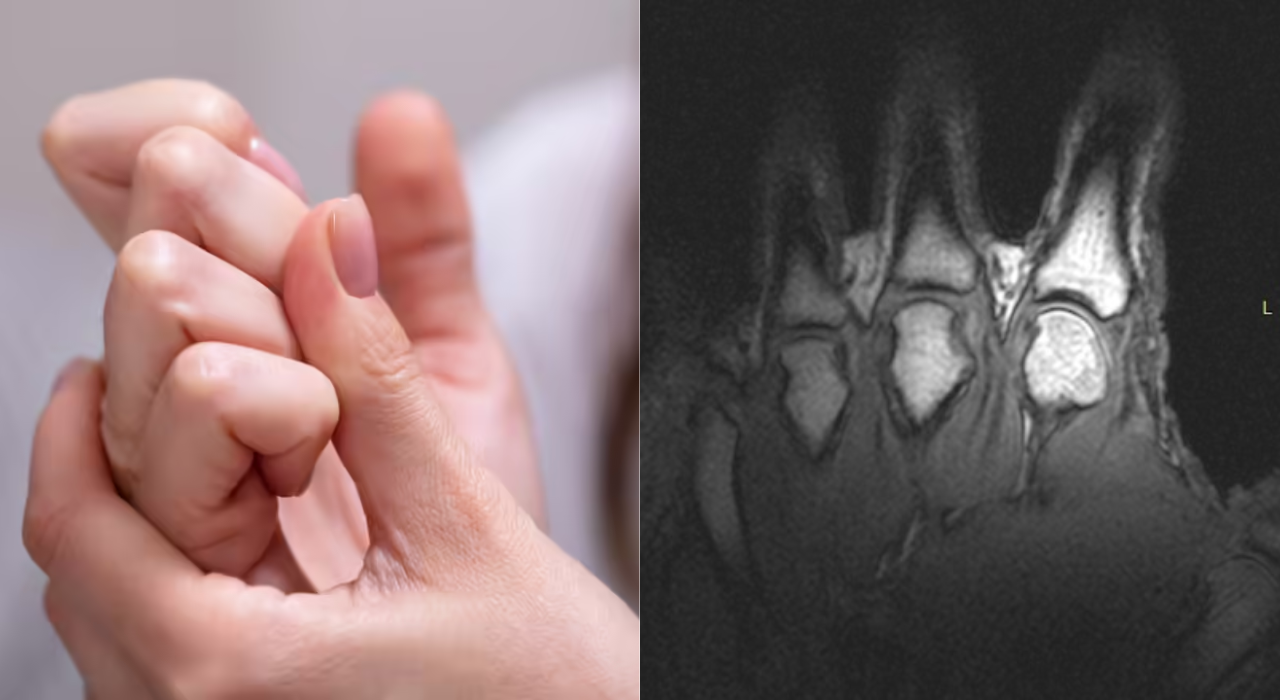

Pant Injury Recap: ‘He was in a lot of pain’